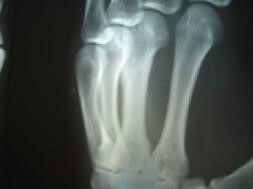

二零零三年三月,邢家秋不堪残酷的摧残,以绝食抗议。在监区队长王晓波、董仑山的指使下,犯人王权、李素安等人在操作间里对他进行围殴。李素安找来一根铁锹把儿,犯人们把他摁倒在地,扒下他的棉裤,分别踩着、摁着他的头、腿、胳膊,李素安抡起锹把猛烈抽打他的腰、臀等部位。因为剧痛,邢家秋用手去挡,手却被李素安抡了一棒,他晕了过去,这时,他的手背肿得像个馒头,不能动。第二天,李素安、金永军对他又一顿毒打,李素安冲着他受伤的手砍了一掌,他痛得坐在地上,此后他的手剧烈疼痛不敢动。

二零零五年六月在沈阳第一监狱拍的X光片子显示邢家秋左手中指骨折